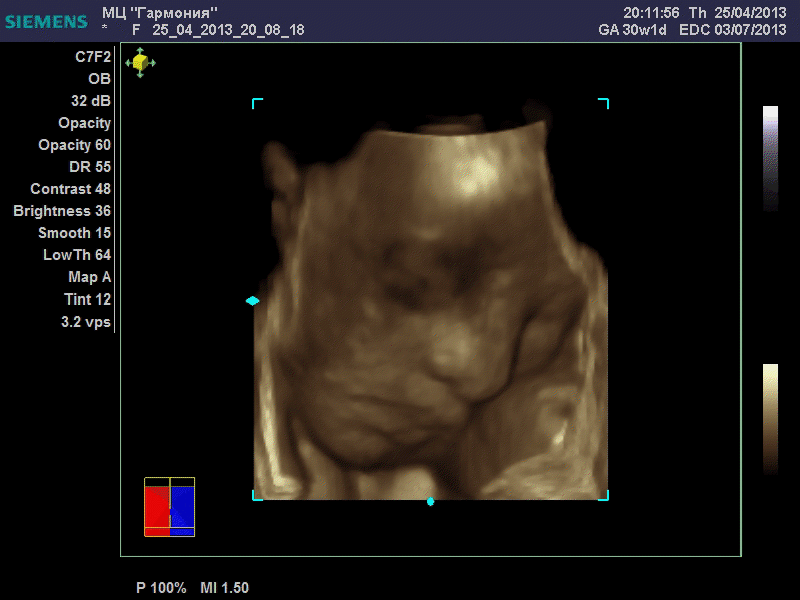

ANGEL*ina, у вас качество очень даже неплохое. GE машины очень хорошие. У моей врачихи такая. Мы сегодня ездили на повторное 3Д узи. Повезло немного больше чем неделю назад. У малыша явно шило в попе. Он кувыркался. За 20 минут несколько раз поменял позицию полностью, и под конец вообще отвернулся. Корд тоже постоянно перед его личиком болтался, да и руками он себя частенько закрывал. Качество фотографий ужасней не придумать.

Вот, пожалуй, самая лучшая фотография.

katerina73 писал(а): Вот, пожалуй, самая лучшая фотография. Катюш, так ваш пупсик зато отлично виден, черты лица отменно видны. Те первые две вчерашние, вторые средней дочки. Со средней черты отлично видны, с этой куклой не понятно..